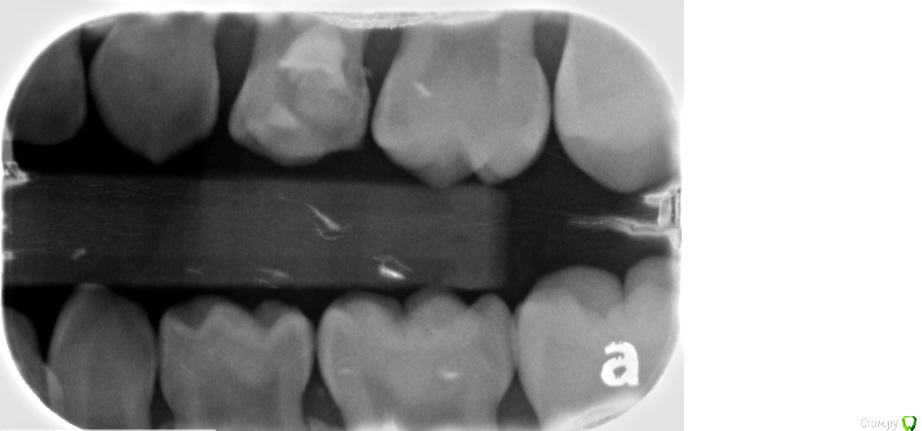

Хотелось бы услышать ваши рекомендации по дальнейшему лечению (ребенку 6 лет).

В первую очередь интересует верхняя левая четверка - в ней разрушилась пломба и часть зуба, сейчас стоит временная полимерная пломба. Есть варант удалить и поставить расширитель, но будет ли хорошей идеей поставить сейчас коронку, или это безнадежно? Сколько она сможет простоять?

Два фото январских и одно от апреля прошлого года (где четверка еще с пломбой).